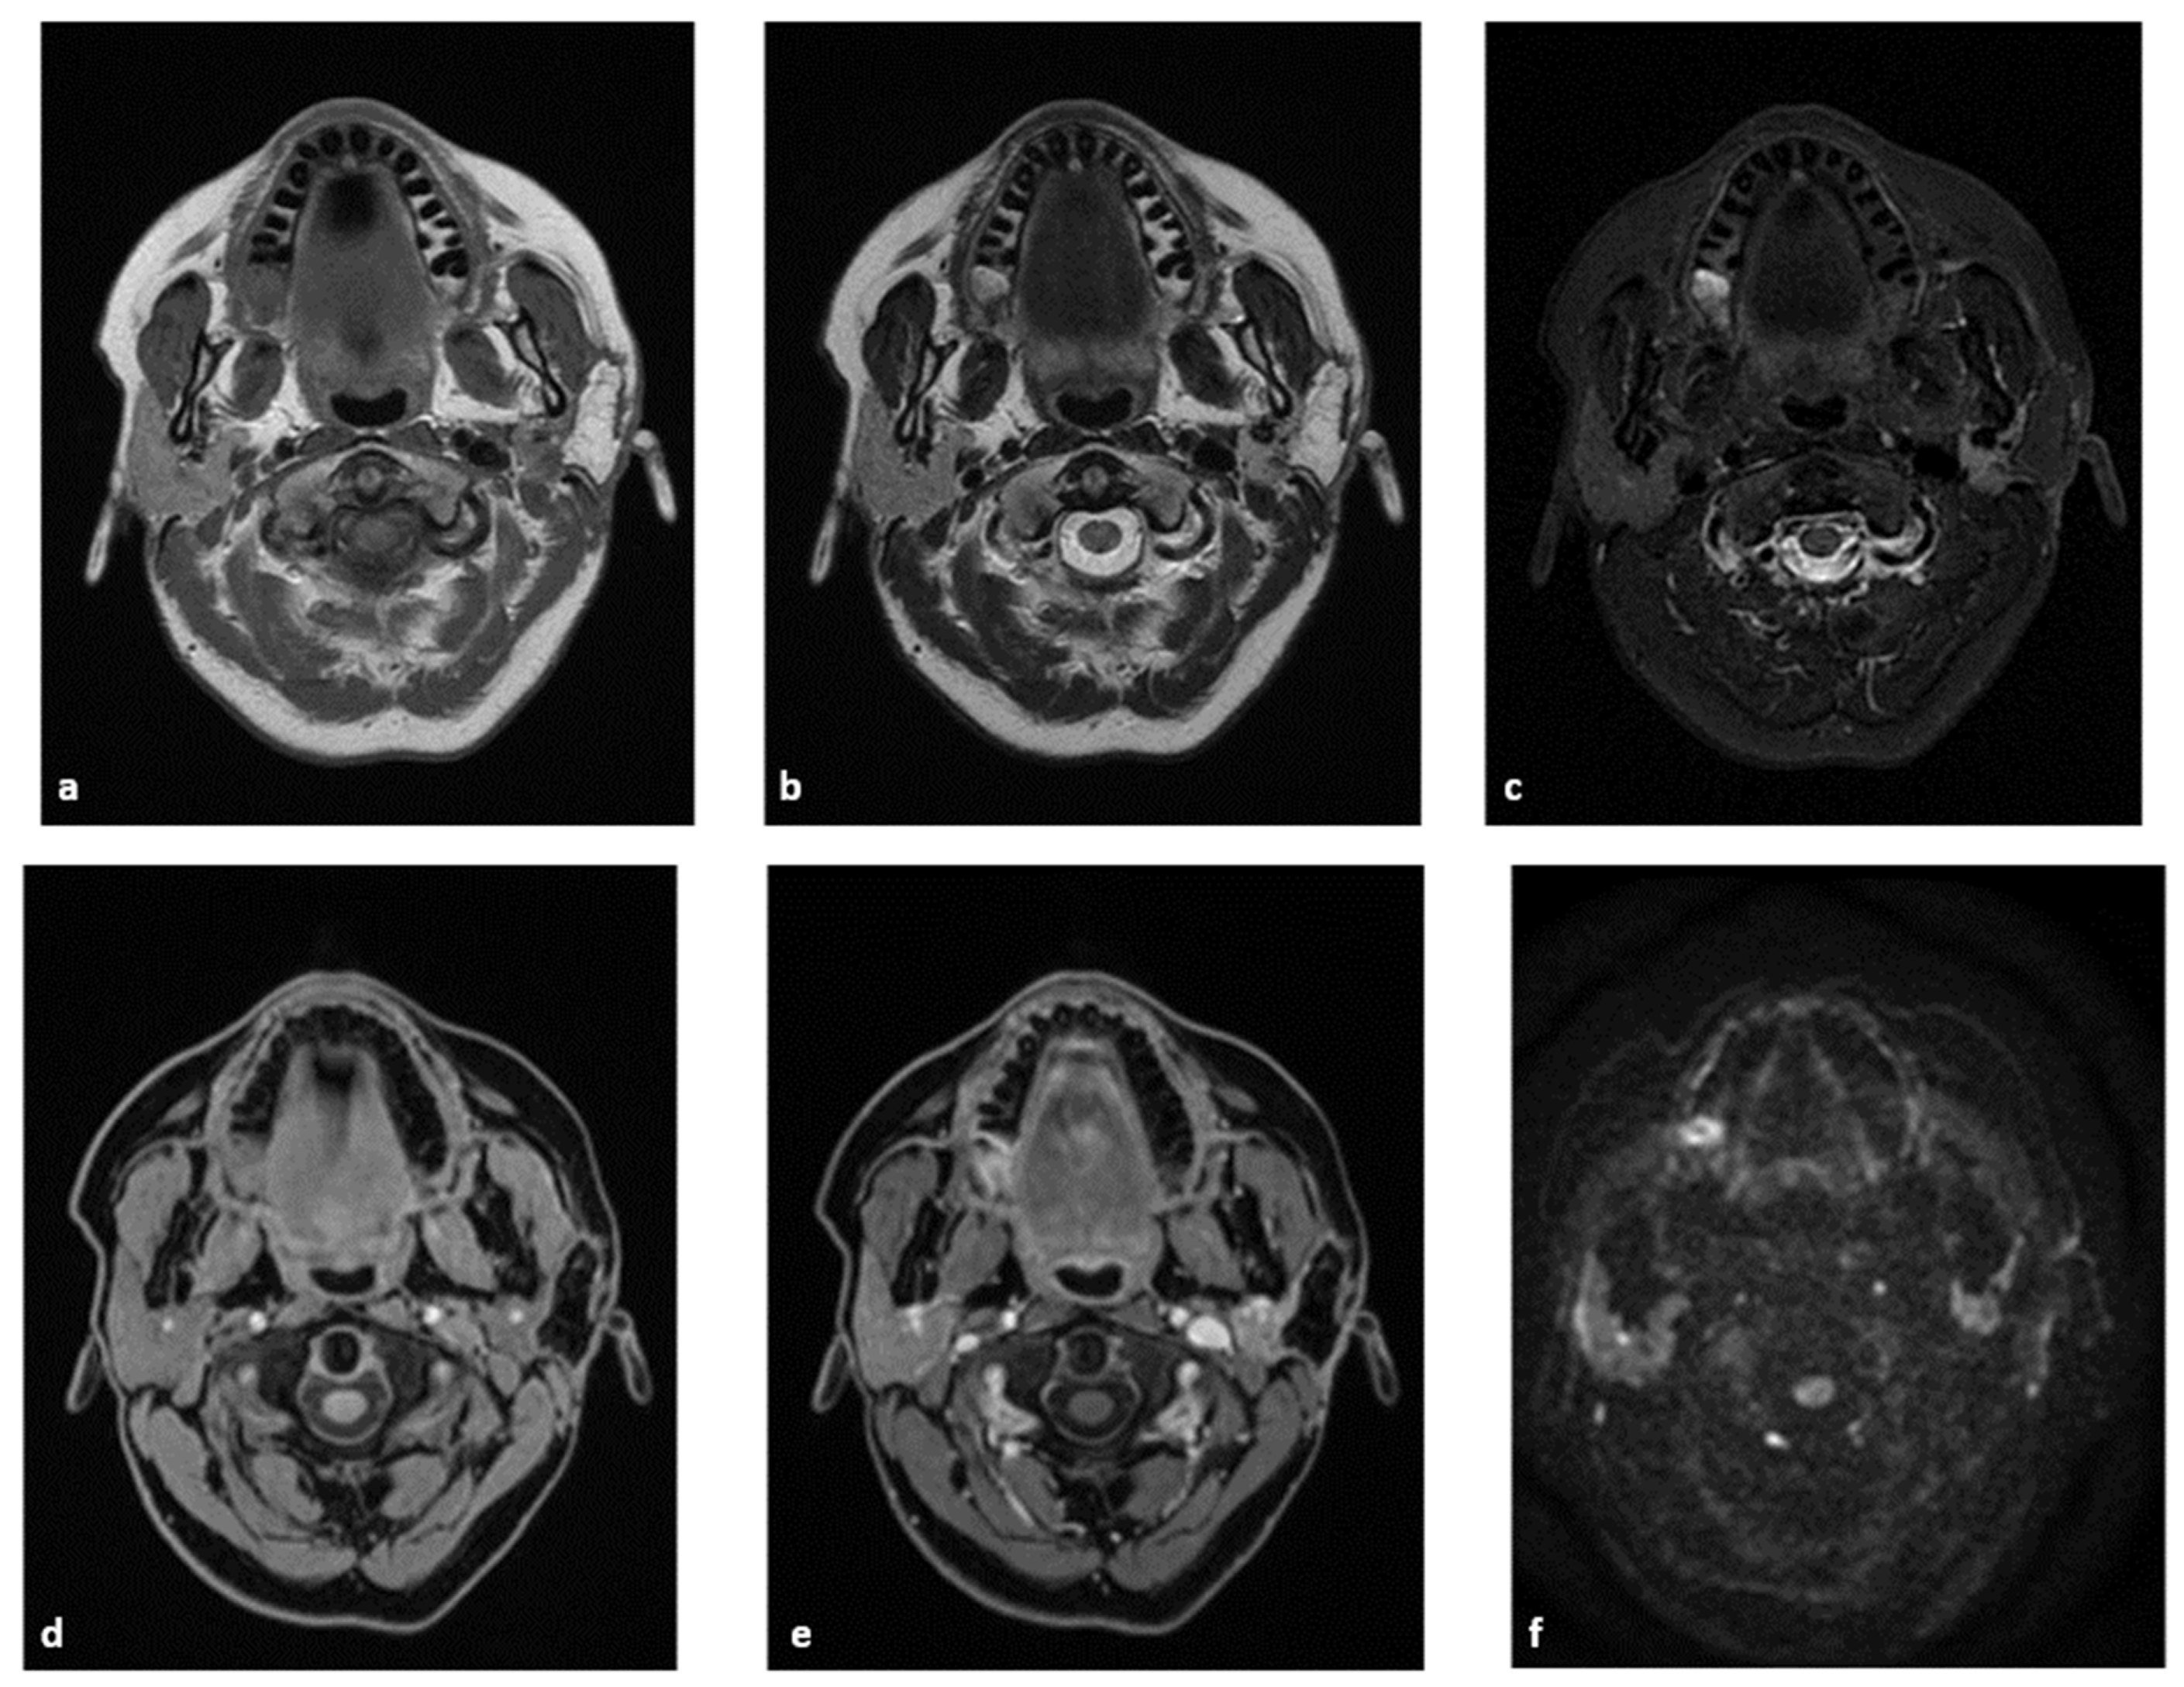

4.1.1. MRI Protocol

4.1.2. MRI Analysis